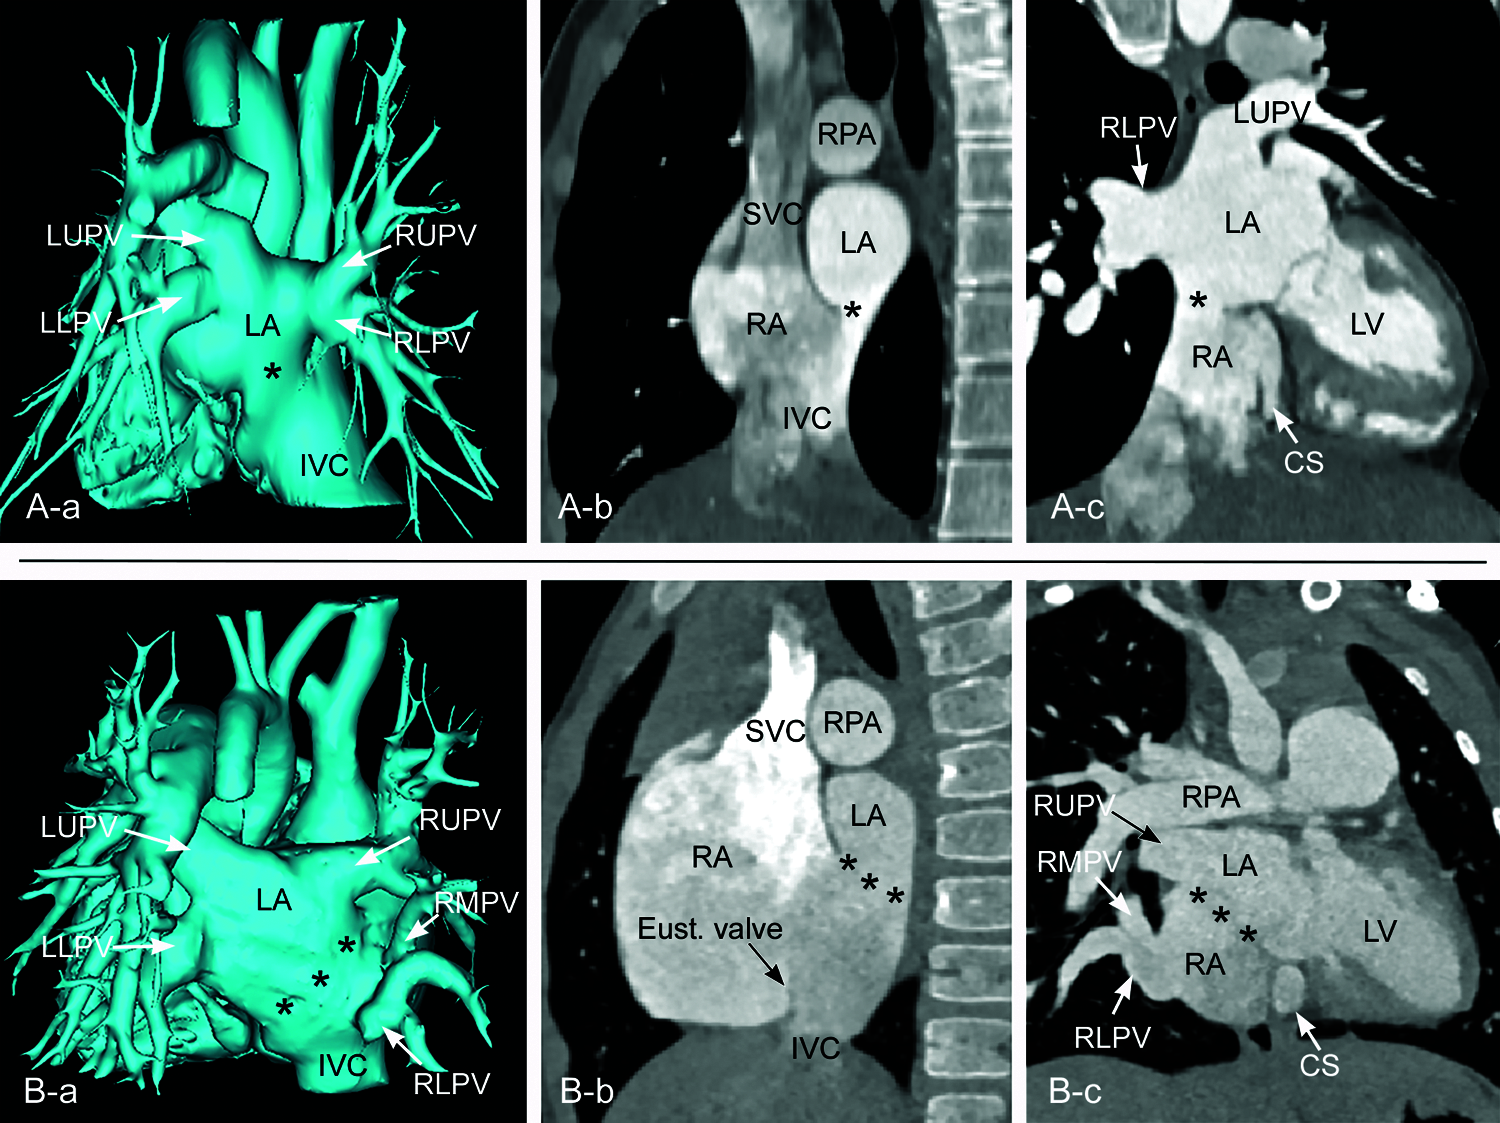

Figure 11: CT angiograms from two different patients showing inferior sinus venosus defects. A. A small defect (asterisk) in the far posterior inferior aspect of the party wall between the right (RA) and left (LA) atria. All pulmonary veins are normally connected to the left atrium. B. A large defect (asterisks) involving the posterior inferior aspect of the party wall between the right and left atria. The right middle and lower pulmonary veins (RMPV and RLPV, respectively) course downward to connect to the lower part of the right atrium. In both cases, the posterior aspect of the inferior vena cava (IVC) is directed toward the left atrium through the defect. In B, the Eustachian valve (Eust.valve) of the inferior vena cava is prominent. CS, coronary sinus; LLPV, left lower pulmonary vein; LUPV, left upper pulmonary vein; LV, left ventricle; RUPV, right upper pulmonary vein; SVC, superior vena cava

Figure 12: Endocardial surface reconstruction of magnetic resonance angiograms from the same patient shown in Fig. 11B, showing the inferior sinus venosus defect. The right anterior wall of the right atrium and ventricle is removed. A is to show the relationship between the fossa ovalis (FO), limbus, coronary sinus ostium (CS) and Eustachian valve (Eust. valve) of the inferior vena cava (IVC). B and C are to show the orifices of the right middle and lower pulmonary veins (RMPV and RLPV, respectively) in relation to the defect and the atrial cavities. A large defect involves the far posterior inferior aspect of the interatrial party wall. The right middle and lower pulmonary veins connect to the lower part of the atrial cavity above the orifice of the inferior vena cava. SVC, superior vena cava

Inferior sinus venosus defects are frequently associated with anomalous connection of the right lower pulmonary vein to the right atrium or inferior vena cavoatrial junction. Some investigators consider the anomalous pulmonary venous connection to be an essential feature of the pathology [25]. However, the inferior sinus venosus defect often occurs with all pulmonary veins normally connected to the left atrium (Fig. 11A) [8,21,26–29]. Therefore, the presence of anomalous pulmonary venous connection to the inferior vena cava or right atrium is not essential for the diagnosis of the inferior sinus venosus defect. Interestingly, inferior sinus venosus defects also may be associated with anomalous connection of the right upper pulmonary vein to the right atrium [30].

In summary, the inferior sinus venosus defect is a congenital malformation that primarily affects the junctional area between the inferior vena cava and the lower part of the sinus venarum. Although frequently associated with an abnormality of the right pulmonary veins, this is not a constant feature required for the diagnosis of an inferior sinus venosus defect. The inferior vena cava appears to override the defective interatrial party wall or septum above or may appear to drain to the left atrium in almost all cases. Importantly, however, this finding is not due to abnormal position or orientation of the inferior vena cava or atrial septum but rather due to the unique alignment of the affected area of the interatrial party wall to the trajectory of the inferior vena cava.